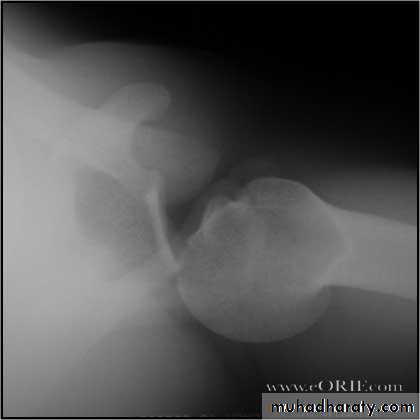

Upper limb

Fall on out stretched hand

xray